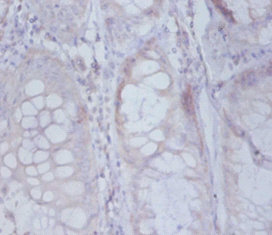

DescriptionRPS19BP1 Polyclonal Antibody. Unconjugated. Raised in: Rabbit.

ApplicationELISA, WB, IHC